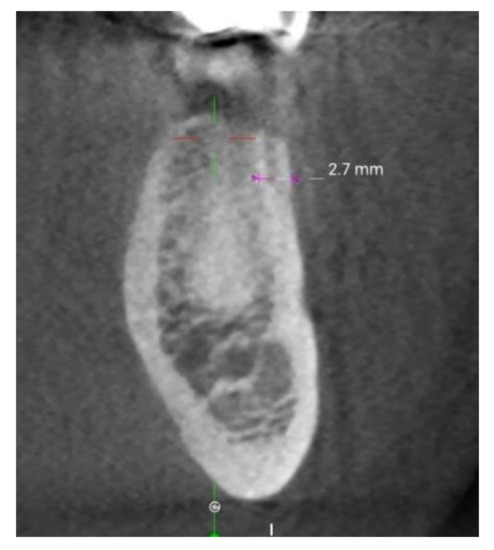

- Ko, Y.C.; Huang, H.L.; Shen, Y.W.; Cai, J.Y.; Fuh, L.J.; Hsu, J.T. Variations in crestal cortical bone thickness at dental implant sites in different regions of the jawbone. Clin. Implant Dent. Relat. Res. 2017, 19, 440–446. [Google Scholar] [CrossRef]

- Gupta, A.; Rathee, S.; Agarwal, J.; Pachar, R.B. Measurement of crestal cortical bone thickness at implant site: A cone beam computed tomography study. J. Contemp. Dent. Pract. 2017, 18, 785–789. [Google Scholar] [CrossRef]